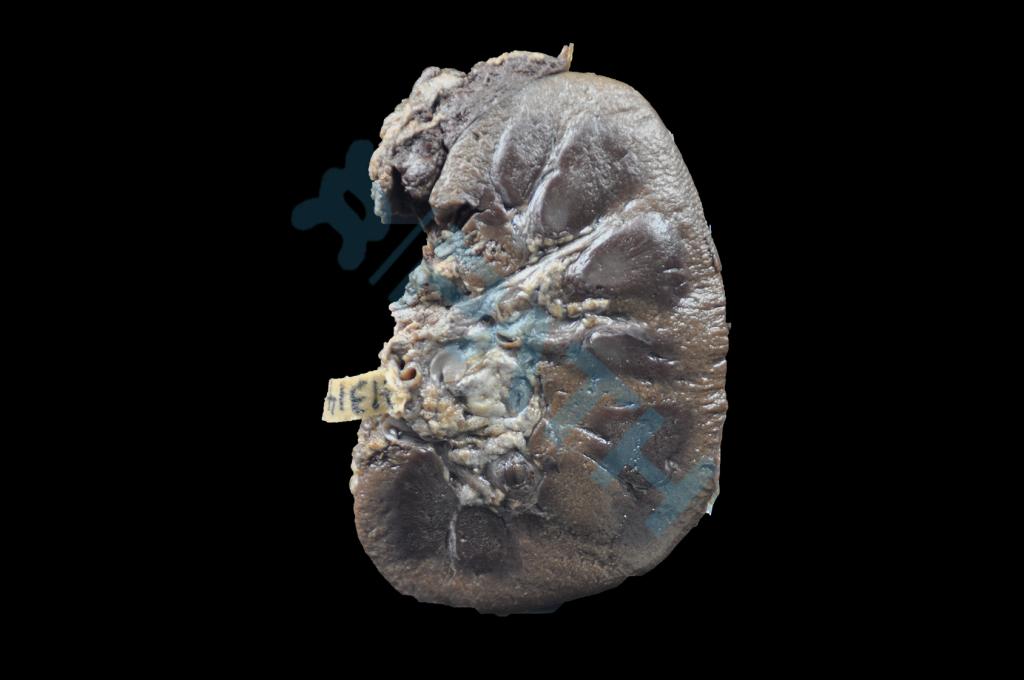

泌尿系统疾病

出血热肾